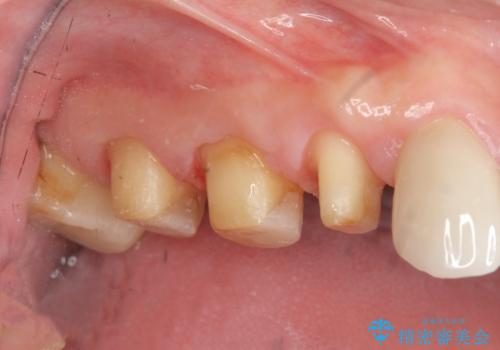

- 重度の歯ぎしり癖で歯がすり減り、見た目・噛み合わせの改善とこれ以上すり減る前の処置を希望され来院されました。

高さが短くなってしまった歯は、安定したクラウンを作るのが難しいため歯ぐきを下げる歯周外科を行ったのちに強度に優れるフルジルコニアクラウンで補綴治療を行います。

すり減ってしまった歯に対し、歯冠長延長術(歯周外科)を行うことで安定したクラウンを製作・装着することが出来ました。